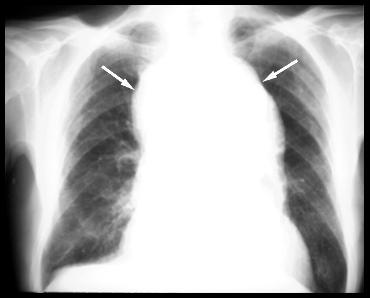

Tranzit esofagian : - deviere importanta la stanga a traheei si esofagului cervical.

Radiografie pulmonara : - masa mediastinala superioara, posibil gusa mare cu extensie retrosternala

- fara leziuni evolutive pleuro-pulmonare